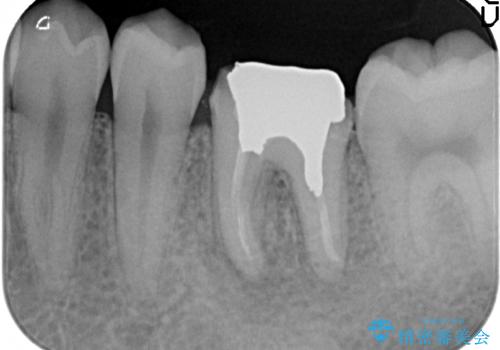

- 他院にて治療途中の歯を診て欲しいといらっしゃった方の症例です。

X線上で根尖病変を認めたため再根管治療を行い、オールセラミッククラウンによる補綴を行いました。